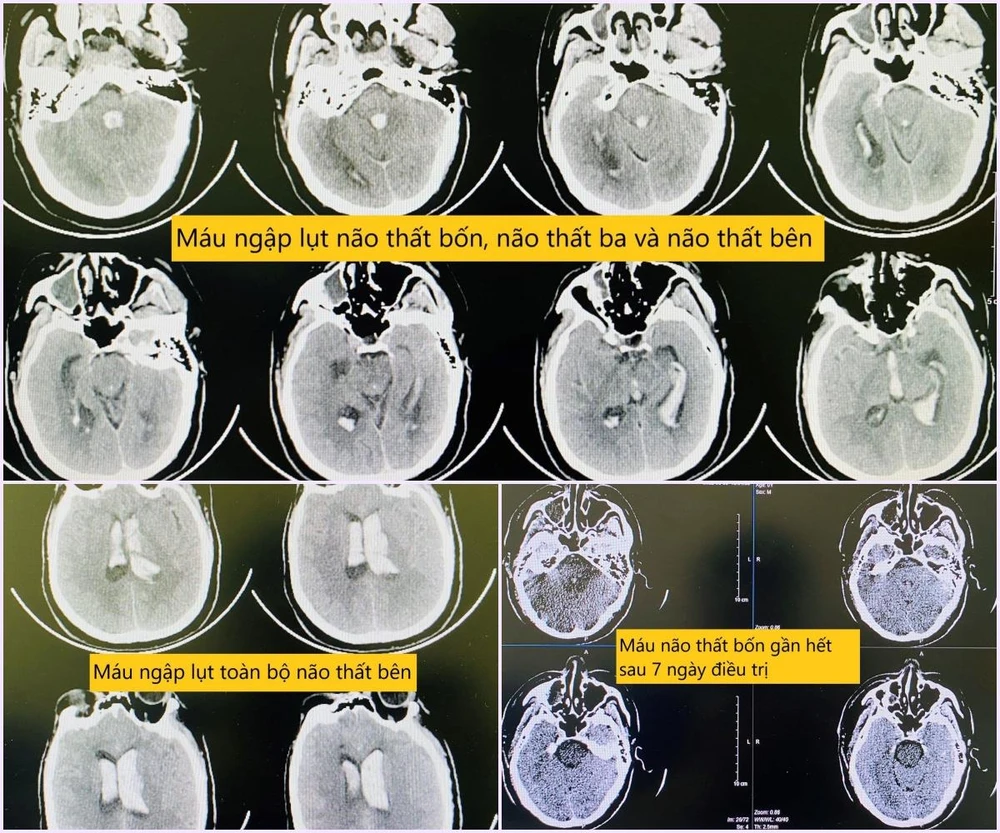

Hình ảnh chụp phim sọ não khi bệnh nhân nhập viện và sau quá trình điều trị. |

Các bác sĩ tiến hành chụp phim sọ não có dựng mạch xác định căn nguyên và đánh giá tổn thương, nhằm có chiến lược điều trị tối ưu.

“Kết quả về cho thấy hình ảnh chảy máu khủng khiếp, "ngập lụt" toàn bộ não thất bên, não thất ba, não thất tư, gây giãn não thất cấp, gây tắc nghẽn lưu thông hệ thống não thất. Với mức độ tổn thương như này nếu không can thiệp gần như chắc chắn tử vong”- bác sĩ Trung tâm Đột quỵ thông tin.

Bệnh nhân được đưa về hồi sức tích cực tại Trung tâm đột quỵ, sau hai ngày thì tỉnh lại Đến ngày thứ 3 bệnh nhân được rút ống thở. Dẫn lưu não thất được rút vào ngày thứ 4. Bệnh nhân được tập phục hồi chức năng hàng ngày tại giường bệnh. Đến hôm nay bệnh nhân đã đứng dậy đi lại được tốt.